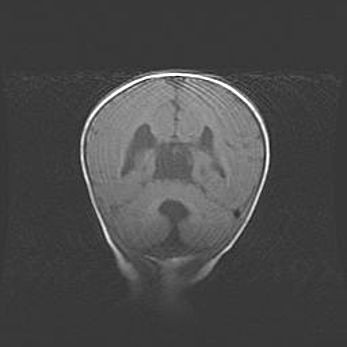

Ниже представлена  галерея МРТ снимков, полученных с применением LMT неонатальных матричных РЧ катушек. Также каждая группа МРТ снимков сопровождается информацией о пациенте (диагноз, возраст, вес, пол, срок гестации) и краткой сопроводительной расшифровкой диагноза.

Мальформация Денди-Уокера. Киста задней черепной ямки.

Агенезия мозолистого тела.

Возраст: 2,5 месяца

Вес: 2420 г

Пол: женский

Окружность головы: 37 см

Срок гестации: 32 недели

Мальформация Денди—Уокера — редкий вид патологии ЦНС, представляющий собой врожденный порок развития каудального отдела ствола и червя мозжечка, ведущий к неполному раскрытию срединной (Мажанди) и латеральных (Лушка) апертур IV желудочка мозга. Для этогно синдрома характерна триада симптомов: гипотрофия червя мозжечка и/или полушарий мозжечка, кисты задней черепной ямки, гидроцефалия различной степени. В 70% случаев порок сочетается и с другими аномалиями головного мозга, в частности с агенезией мозолистого тела.